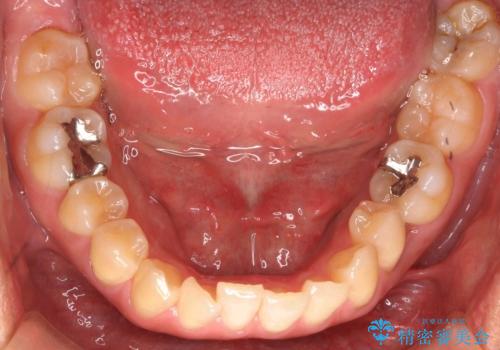

埋まっている奥歯を引っ張り出す インビザライン矯正

- 前歯のがたつきと左下の歯がうまっているとのことで、矯正治療を希望されました。

埋まっている奥歯を並べることで、その後ろの倒れ込んだ歯を整直させることができました。

引っ張り出すことはマウスピース矯正では難しい為、埋まっている歯を並べるスペース確保と、引っ張り出すのに、ワイヤーを用いた部分矯正を行なっています。

埋まっていた歯をしっかり引っ張り出すことができ、また、前歯の見た目も非常に良くなりました。

ワイヤー矯正を奥歯の部分的に行なっただけで、治療の大半をマウスピース矯正で行うことができ、非常に喜んでいただきました。